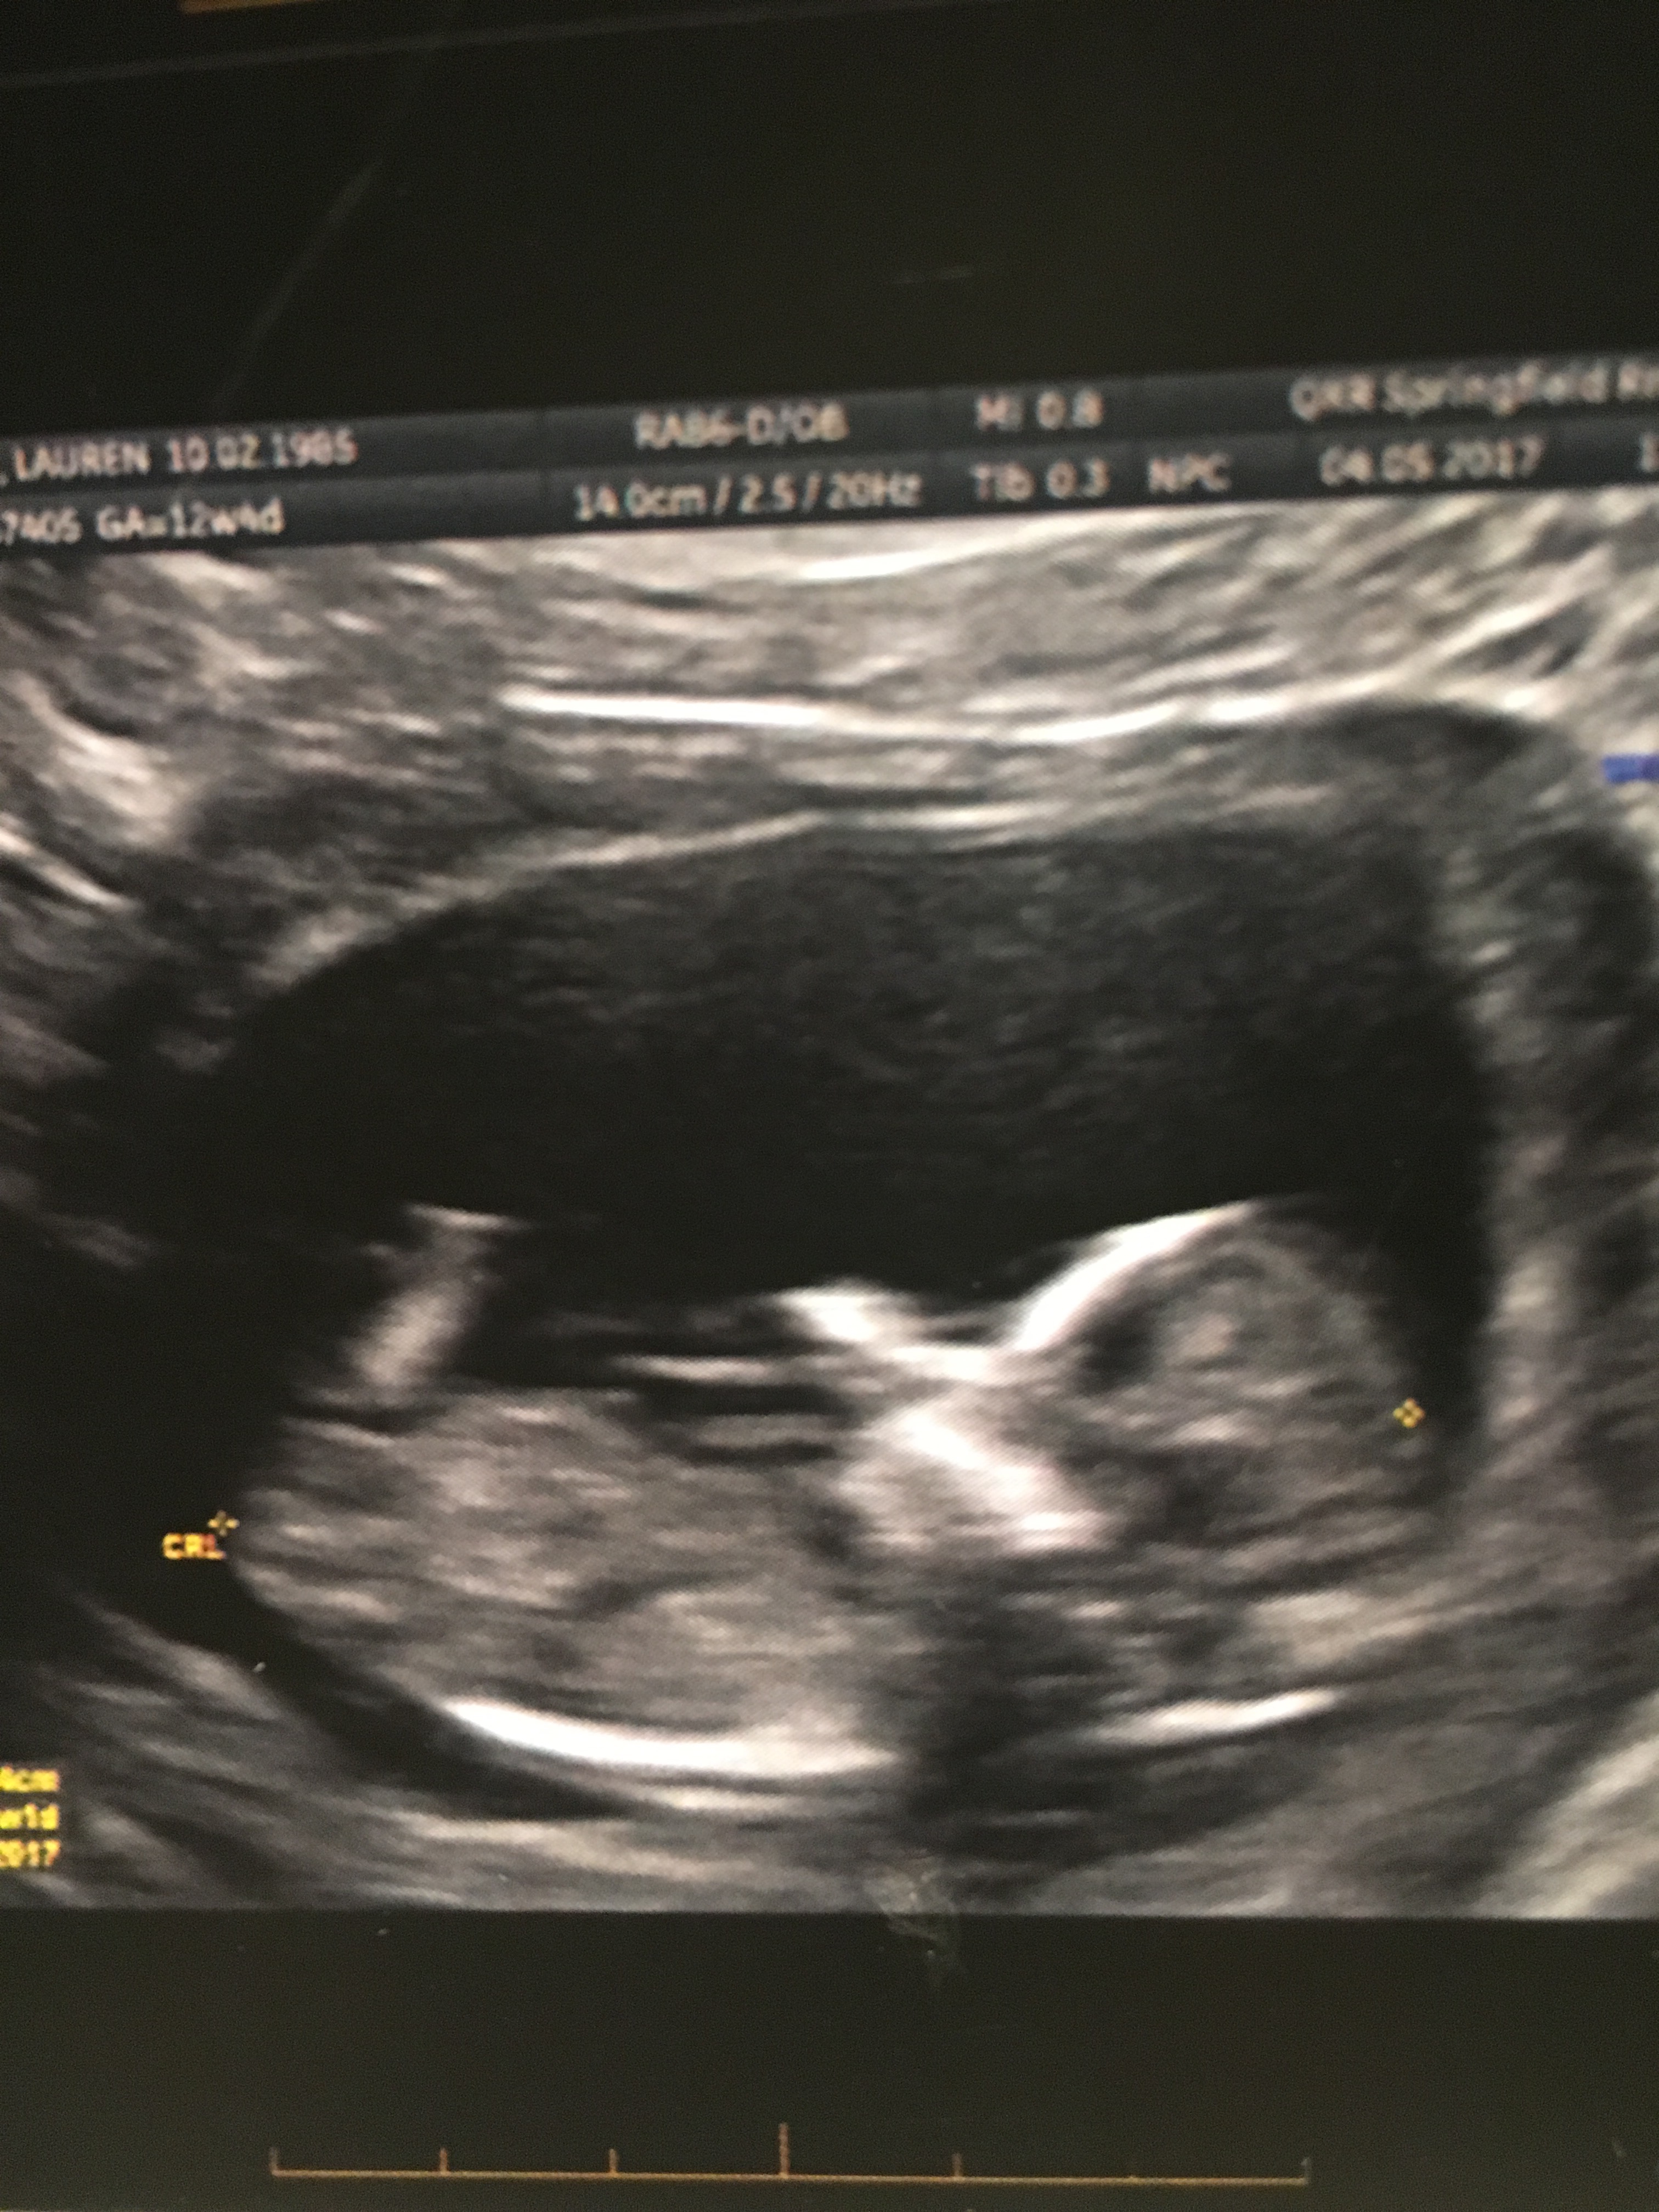

What are your thoughts? I was 13 weeks here! Attachment 36210 Sent from my iPhone using Tapatalk

Maybe girl